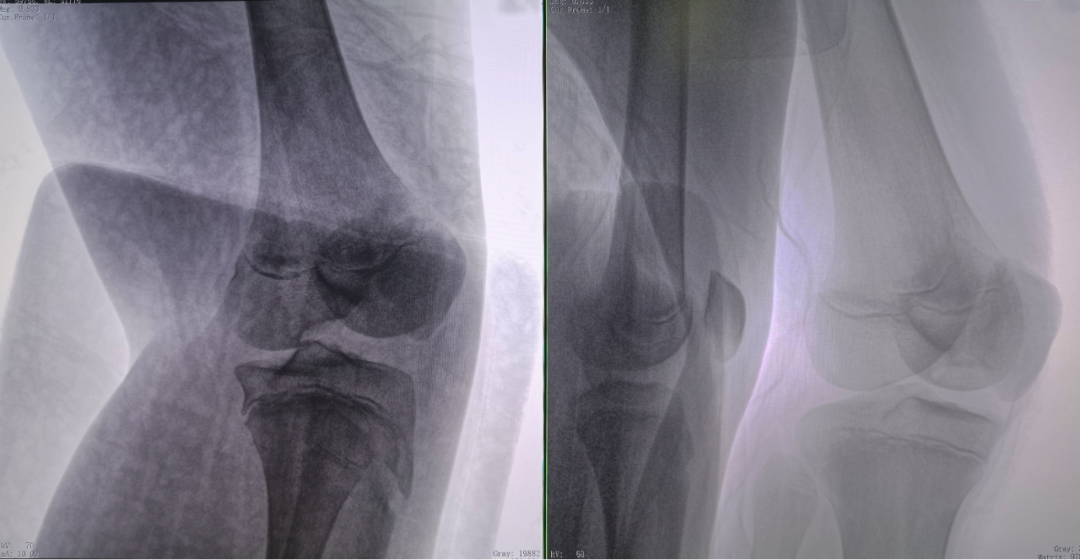

病例1:右側(cè)股骨遠(yuǎn)端骨骺骨病(13歲)

二維影像看不到病灶點(diǎn)

三維切面影像可以看出病灶點(diǎn)